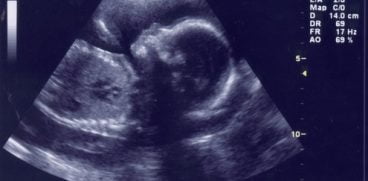

Placenta: rolul ei in sarcina si afectiuni care pot aparea. Placenta are un rol esential in sarcina si in dezvoltarea copilului. Ea se dezvolta in uter, fiind atasata de peretii acestuia si furnizeaza oxigen, dar si alte substante nutritive necesare fetusului.

Tot de la placenta se formeaza si cordonul ombilical al copilului. In momentul nasterii, ea este eliminata, iar multe femei aleg chiar sa o pastreze, pentru consum, avand numeroase proprietati nutritive. Totusi, sanatatea placentei este si ea asigurata de numerosi factori.